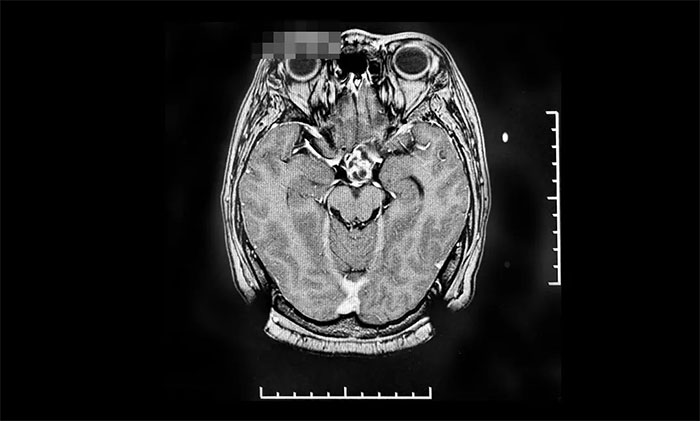

▲ 腫瘤復(fù)發(fā)后,來(lái)我院行伽瑪?shù)吨委熐坝跋?/font>

2022年8月,因視力下降就醫(yī),復(fù)查提示腫瘤復(fù)發(fā),遂來(lái)上海藍(lán)十字腦科醫(yī)院進(jìn)行伽瑪?shù)吨委,后順利出院。今?0月,患者來(lái)院復(fù)查,影像學(xué)檢查提示腫瘤體積較治療前明顯縮小,患者視力較前改善,控制良好,陳琦主任叮囑其繼續(xù)隨訪觀察。